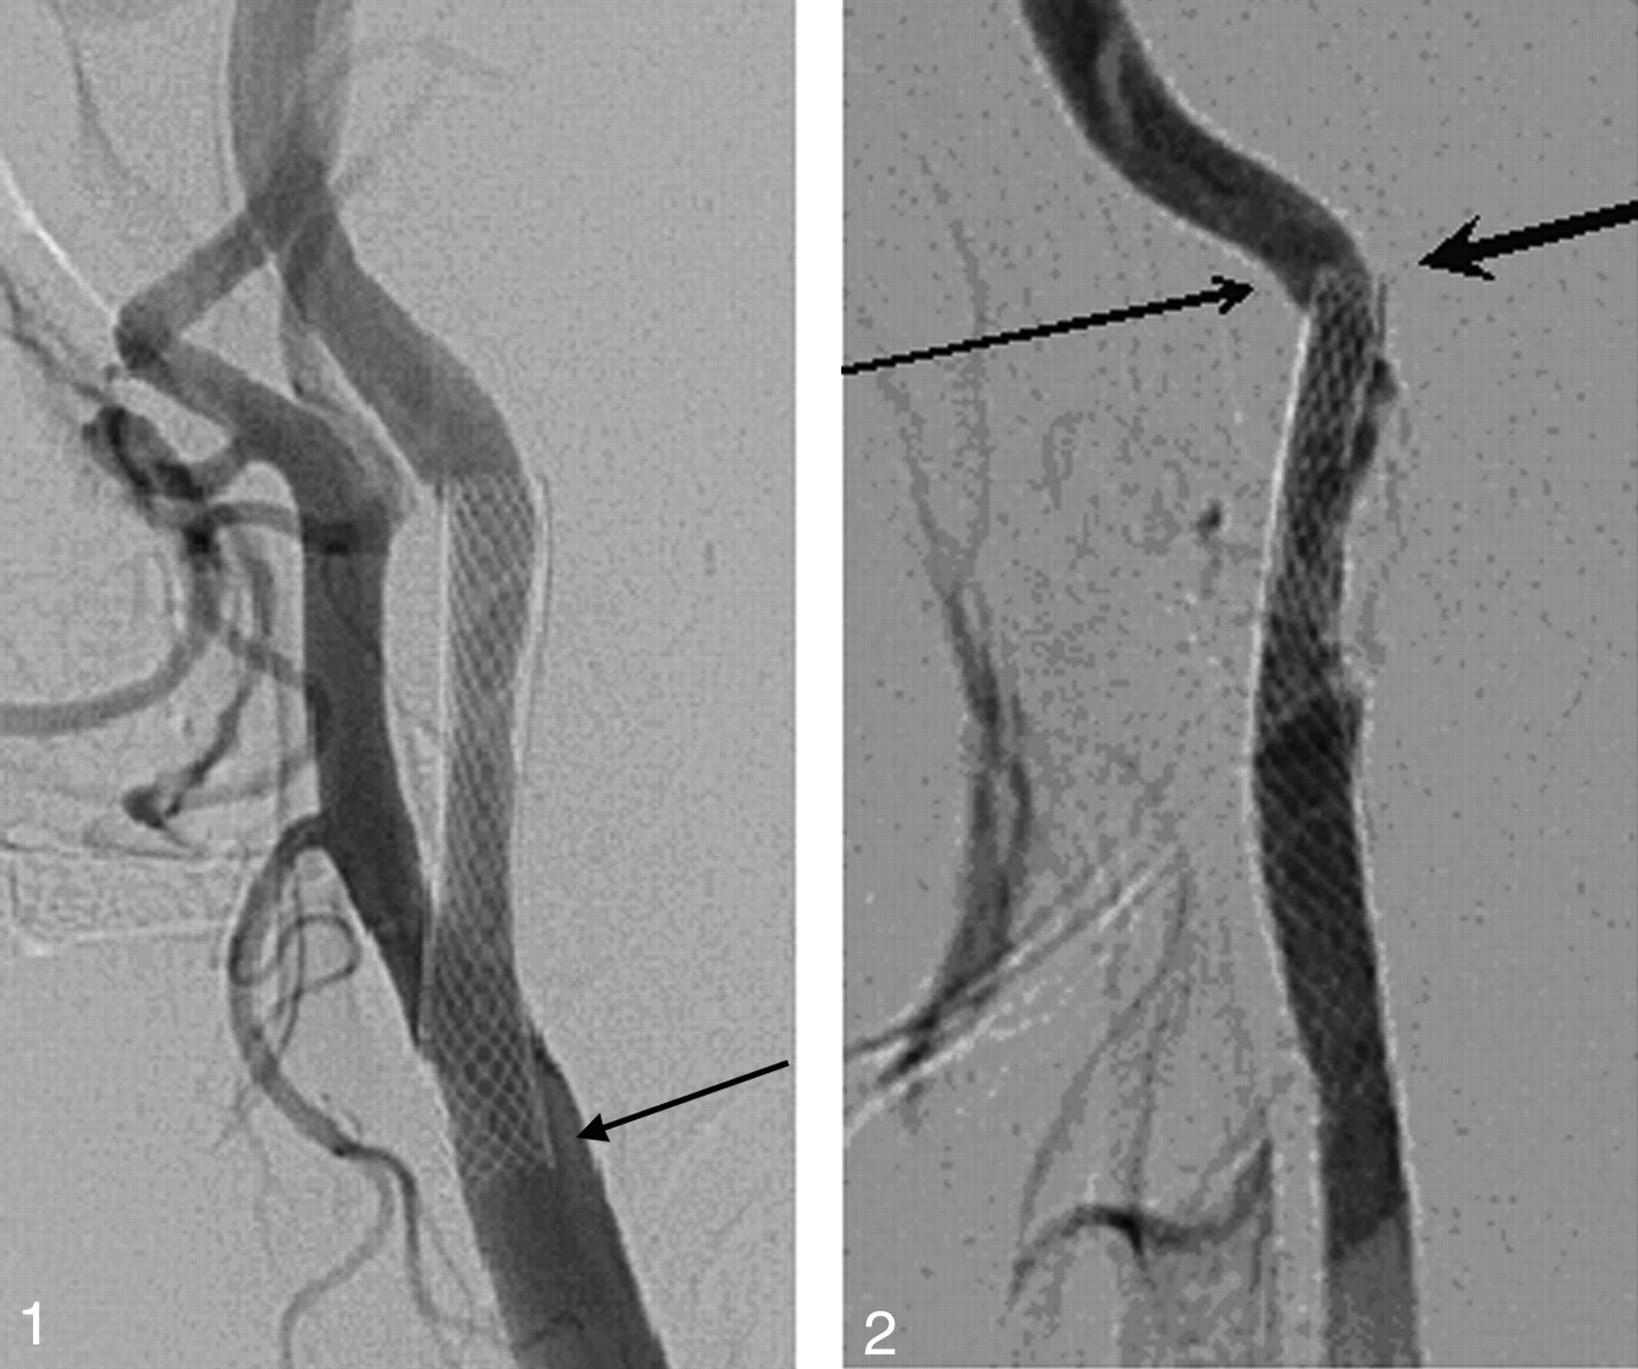

Patient 5. An asymptomatic 77-year-old man. A left carotid angiogram (lateral view) showing an incomplete stent apposition at the proximal stent edge (arrow).